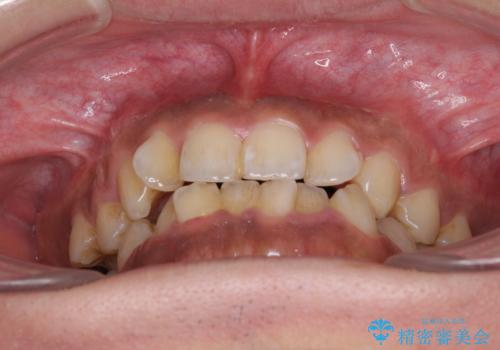

- 前歯のデコボコを気にして来院された患者様です。

前歯が90度近く捻れていたため、しっかりと治すことを考えるとワイヤー矯正の方がおすすめではありましたが、本人の希望によりインビザラインを用いて矯正治療を行うこととしました。

途中2年強の来院がなく、改善されていたデコボコが元に戻ったり、装着時間が不足しており前歯のデコボコは十分に改善することはできませんでしたが、5年間の有効期限内で可能な限り歯列を整えることができました。